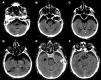

Coma secundario a neumoencéfalo a tensión en fosa posterior

Coma due to tension pneumocephalus in the posterior fossae